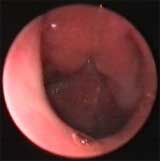

Обострение хронического аденоидита (эпифарингоскопия — эндоскоп 70°).